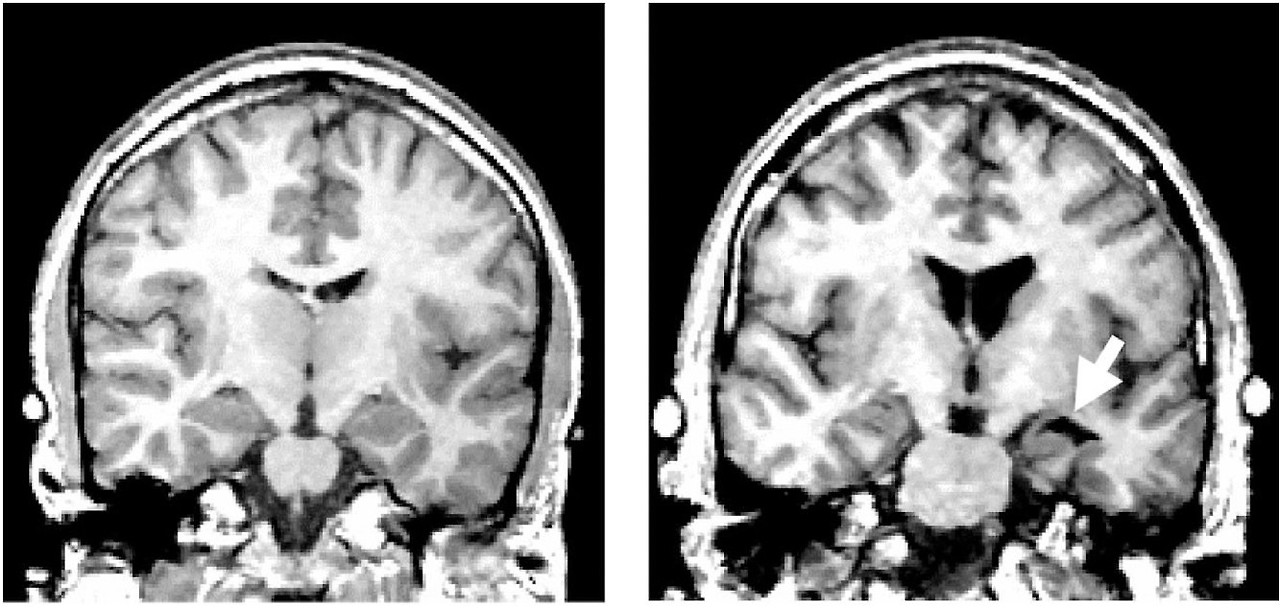

2.jpg [그림1] 대조군(Control) vs 조현병 환자(Schizophrenia patient)의 MRI[3]

[그림1]은 대조군의 뇌 MRI(왼쪽)와 조현병 환자의 뇌 MRI(오른쪽)을 보여주고 있습니다. 조현병 환자의 경우, 대조군에 비해 실비우스열(Sylvian fissure) 부분과 편도체를 감싸고 있는 관자뿔(temporal horn, 흰색 화살표) 부분에 뇌척수액(CSF, black)이 더 많습니다. 또한, 조현병 환자의 MRI 사진 정중앙에 있는 측뇌실(lateral ventricle) 부분에 검은색 부분이 훨씬 더 큰 것을 볼 수 있으며 이는 대조군에 비해 조현병 환자의 측뇌실 부분이 확장되었기 때문입니다[3]. 실제로 여러 연구 결과에 의하면 조현병 환자들은 건강한 대조군에 비해 뇌실이 확장되고 대뇌피질은 위축되며 회백질 부피는 감소되는 해부학적 차이가 있다고 합니다. 이러한 뇌 부위들의 이상도 조현병의 원인과 관련이 있을 거라고 생각되고 있습니다[4].